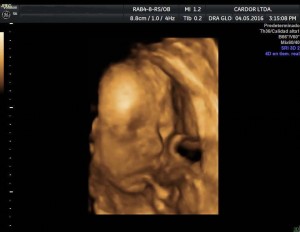

A partir del segundo trimestre de embarazo, entre las semanas 13 y 27, sus órganos van madurando y adquieren mayor complejidad.

Vea la siguiente presentación. Imágenes 100% Cardor: